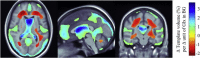

Cognitive impairment and brain injury are common in people with HIV/AIDS, even when viral replication is effectively suppressed with combined antiretroviral therapies (cART). Metabolic and structural abnormalities may promote cognitive decline, but we know little about how these measures relate in people on stable cART. Here we used tensor-based morphometry (TBM) to reveal the 3D profile of regional brain volume variations in 210 HIV + patients scanned with whole-brain MRI at 1.5 T (mean age: 48.6 ± 8.4 years; all receiving cART). We identified brain regions where the degree of atrophy was related to HIV clinical measures and cerebral metabolite levels assessed with magnetic resonance spectroscopy (MRS). Regional brain volume reduction was linked to lower nadir CD4 + count, with a 1-2% white matter volume reduction for each 25-point reduction in nadir CD4 +. Even so, brain volume measured by TBM showed no detectable association with current CD4 + count, AIDS Dementia Complex (ADC) stage, HIV RNA load in plasma or cerebrospinal fluid (CSF), duration of HIV infection, antiretroviral CNS penetration-effectiveness (CPE) scores, or years on cART, after controlling for demographic factors, and for multiple comparisons. Elevated glutamate and glutamine (Glx) and lower N-acetylaspartate (NAA) in the frontal white matter, basal ganglia, and mid frontal cortex - were associated with lower white matter, putamen and thalamus volumes, and ventricular and CSF space expansion. Reductions in brain volumes in the setting of chronic and stable disease are strongly linked to a history of immunosuppression, suggesting that delays in initiating cART may result in imminent and irreversible brain damage.